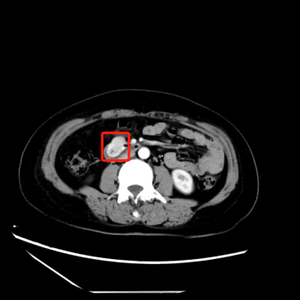

胡兵教授仔细问诊后,建议樊女士完善术前腹部增强CT和超声内镜检查。增强CT及超声内镜均提示:十二指肠水平段见软组织包块,向腔外膨胀性生长,边界清楚,未见淋巴结肿大及远处转移,十二指肠管腔轻度稍狭窄改变。